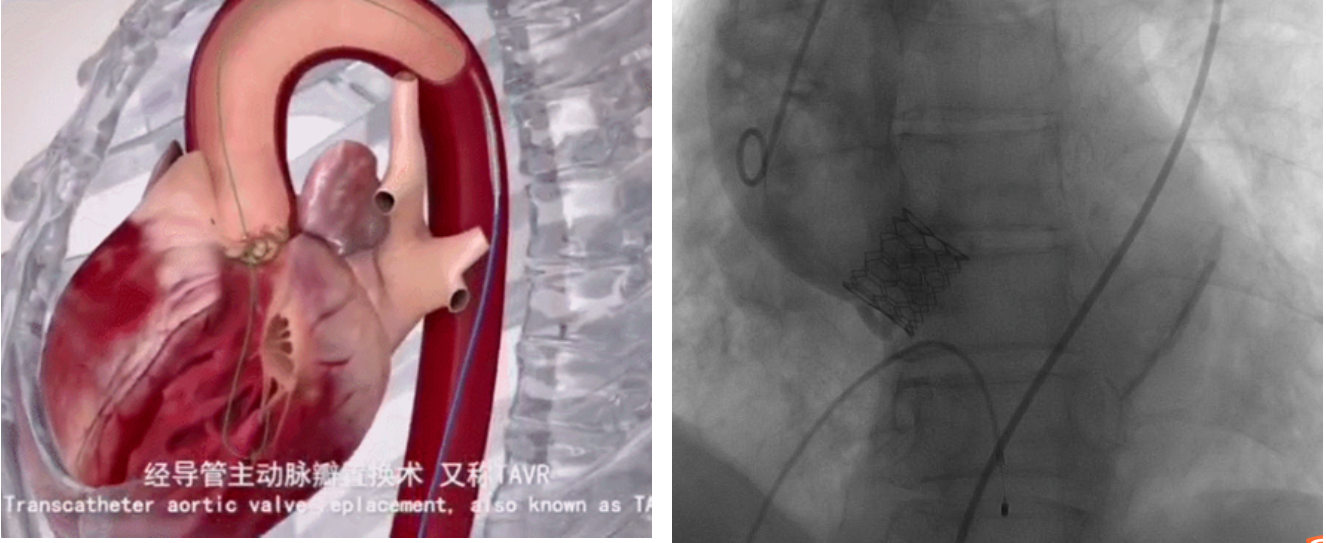

开胸主动脉瓣置换术是治疗主动脉瓣重度狭窄的标准方案,但一些高龄、存在严重合并症的患者可能无法耐受手术,故经导管主动脉瓣置换术(TAVR/TAVI)应运而生。

TAVI是将人工生物瓣膜通过介入导管输送到心脏主动脉瓣区打开,完成人工瓣膜的植入,恢复瓣膜功能的一种技术,具有创伤小、术后恢复快等优点。